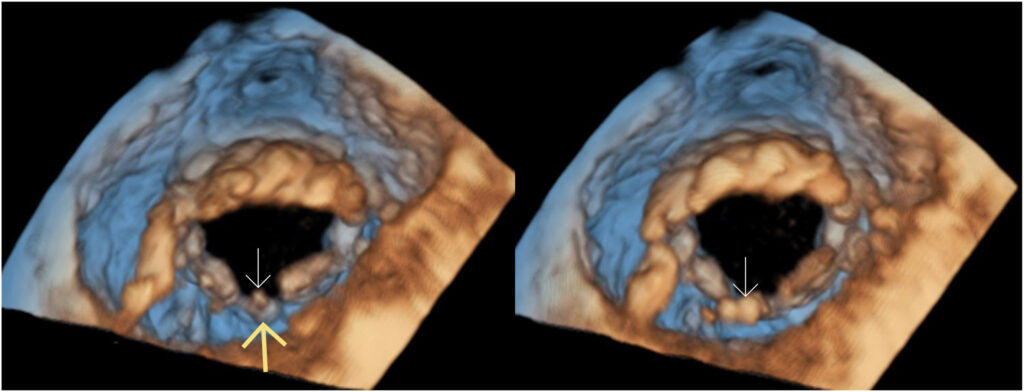

Dois músculos papilares foram observados em posições habituais e um pequeno folheto comissural com cordoalhas aderidas à ele foi identificado entre os dois folhetos posteriores .

Os achados, portanto, corroboraram a presença de uma comissura anatômica e uma VMi trivalvular congênita.

Foi documentada a presença de cordoalha aderida à região do cleft que dividia o folheto posterior em duas partes. 02 músculos papilares foram observados, em posições habituais.

A literatura menciona tal situação como “cleft chordae“, porém este termo faz menção à cordoalhas que se conectam às invaginações que separam os dois folhetos e estão aderidas nas bordas dos folhetos (e não nas comissuras), ao contrário do observado no CASO 02.

Quanto às invaginações (“cleft like indentations“), estas podem ser caracterizadas quando na presença de uma profundidade de até 50% entre os segmentos adjacentes. Na maior parte dos casos, são observadas entre os segmentos P1/P2 e entre os segmentos P2/P3, resultando em uma divisão assimétrica do folheto posterior, bem como uma distância também assimétrica entre a invaginação e as comissuras.